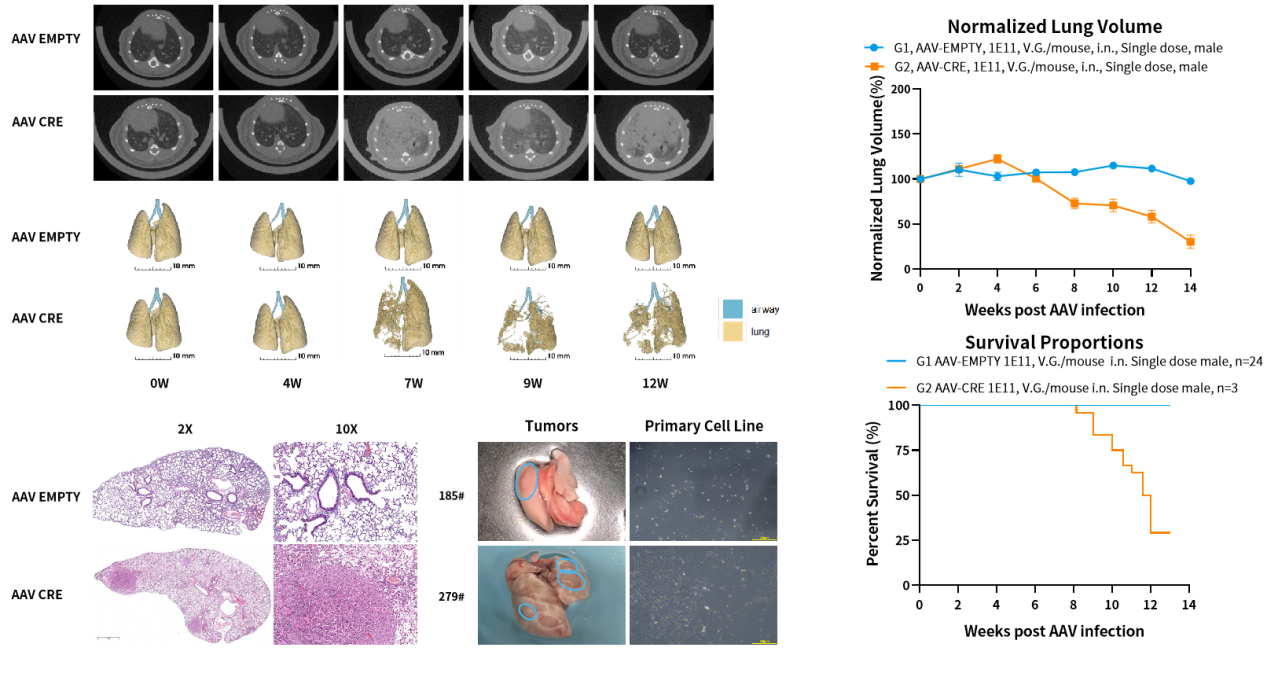

Stk11/EGFP/Kras-LSL-G12D小鼠是一种原发肺癌小鼠模型,包含了KRAS基因突变、EGFP过表达与STK11蛋白缺失。EGFR的高表达或异常激活与包括非小细胞肺癌(NSCLC)在内的多种癌症的肿瘤进展和治疗耐药有关,STK11突变经常发生在非小细胞肺癌中(发生率超过10%),Kras 突变在肺癌(NSCLC)占34%,以非小细胞肺癌占比较多,肺鳞癌中占比较少。KRAS突变基因与EGFP过表达基因的上游含有lox-stop-lox终止序列,其在没有cre重组酶的条件下是不表达的;Stk11也需要Cre的存在才能发生敲除。通过使用AAV-CRE对小鼠进行诱导,即可使小鼠产生肿瘤。

验证数据:

图1 Stk11/EGFP/Kras-LSL-G12D原发肺癌小鼠模型可通过AAV-CRE诱导引发肺癌。

图2. Stk11/EGFP/Kras-LSL-G12D瘤块来源细胞系的抗肿瘤药效评价